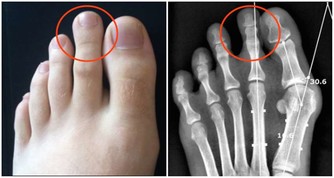

2.中老年人膝蓋疼是欠抽

在大會現場,《大河健康報》記者的左膝髕骨軟化,打過幾次封閉,至今上樓、爬山甚為不便。趙之心老師說:

「20多歲的年輕人就髕骨軟化?這是60歲以上的老人才會有的病。你給我靠牆罰站去。」

1保膝蓋靠罰站,打封閉不好使

趙之心是這樣讓記者罰站的:背部靠牆站好,雙腿下蹲,作「小半蹲」訓練。

記者堅持了一兩分鐘,休息30秒接著「蹲」,記者在從蹲姿到站立時,膝關節明顯有力了。趙之心說:

「膝關節有問題,打封閉是不好使的。這就像你天天喝自來水,突然一天喝不幹凈的河水,打了封閉,髒東西進去,再也休想清理乾淨。只有運動才能刺激關節液的產生。」

「這個動作我能堅持看完一場足球賽,你每天練上20~40分鐘,一個月治不好你的病,我請你去北京吃大餐。」

2膝蓋不好是欠抽

第一拍用手拍到膝蓋正面,第二拍拍膝關節外側面,第三拍拍膝關節內側。每個部位各拍30下。

「膝關節問題,不僅缺練,還欠抽!」

為什麼拍打膝蓋會有止痛、強健膝蓋的效果呢?趙之心老師說:

「膝關節沒有足夠的血管,經常拍打就會刺激血液供應和關節液的產生,本來膝蓋很涼,拍完大家就感覺好多了。」